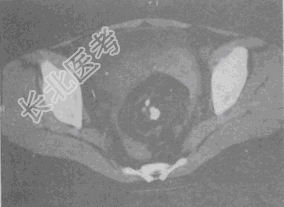

- 单项选择题女,52岁, 下腹部胀痛,B超提示盆腔占位, CT扫描如图所示,盆腔内见囊实性肿块, 其内CT值不均,从-120至300Hu不等, 最可能的诊断是

A、盆腔畸胎瘤

B、盆腔结核

C、子宫肌瘤

D、卵巢囊肿

E、卵巢黏液瘤